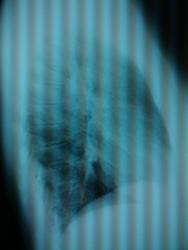

Одну тенюшечку откопала, которой нет на архивных снимках. К фтизиатру напрашивается.

а как Вам это место?

Не надо стесняться, покрутите под скопией, бока сделайте, верхушки, вдохи выдохи. Установка я смотрю хорошая...